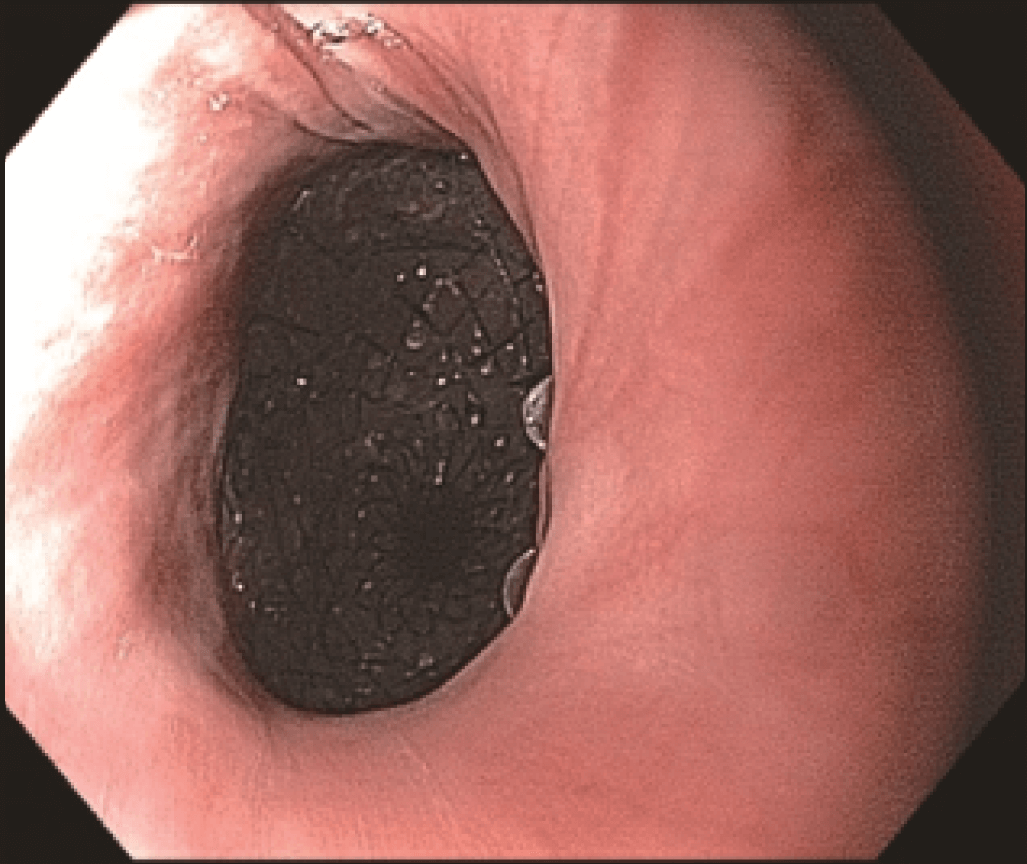

Endoscopic evaluation identified a stricture located at the proximal end of the SEMS (Figures 3 and 4) at 20 cm from the incisors, apparently caused by tumor growth. The upper esophageal sphincter was located at 16 cm from the incisors.

The stricture was located at the uncovered proximal end of the initial SEMS, placed at the cervical esophagus. The stricture was hard and did not allow the passage of the 4.9 mm scope.

However, the three marks at the HANAROSTENT’s distal, medial and proximal ends were easily seen under fluoroscopic guidance, and were valuable in ensuring acurate deployment, just distal to the upper esophageal sphincter (Figure 5). The distal end of the HANAROSTENT remained in the patent portion of the previous stent. The endoscopic view of the SEMS proximal end can be observed in the images below (Figures 6, 7 and 8).